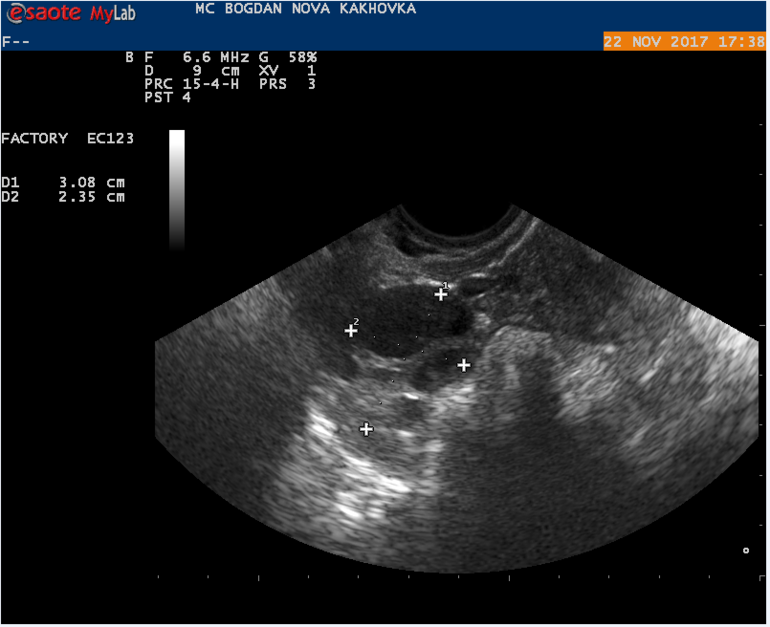

Мой результат УЗИ на 16 ДЦ Кто что может сказать? Тест на О положительный на 13 и 14 ДЦ.

Могли желтое тело не увидеть, а мог и сдуться фоликул, и не было овуляции. А то что эндометрий хороший - еще не показатель, у меня при здутии фолликула и при лютеинизации фолликула он тоже был отличный и соответствовал второй фазе.

в протоколе узи не слова о наличии доминантного фолликула, поэтому вряд ли была или будет овуляция в ближайшие дни

судя по узи овуляции не было,доминантного фолликула нет. хотя желтое тело может позже сформироваться